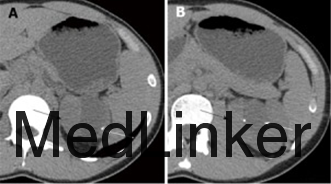

查体:左肾区叩痛(+),腹部无明显压痛、反跳痛,余未见明显异常。 辅查:我院腹部CT平扫+增强示:左肾囊实性肿块,大小约68X42mm,实性部分增强后在皮髓质期明显强化,后强化减低,囊性部分未见明显强化,考虑左肾恶性肿瘤并囊性变。余实验室检查未见明显异常。

入院诊断:左肾肿物:左肾癌?入院后行左肾肿物切除术,术中见一类球星肿物位于左肾下极,大小约6x5x4cm,颜色较正常肾实质深,质韧,表面较光滑,边界尚清晰,无明显粘连。术后病理示:(左肾盂旁肿物)肾类癌。